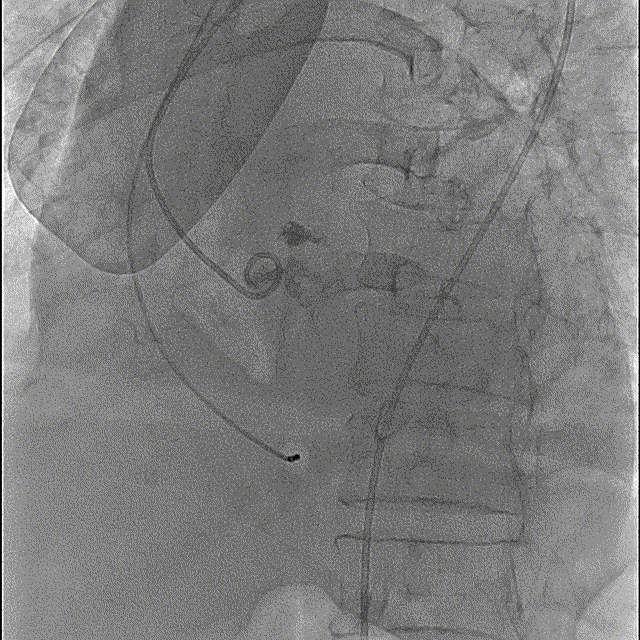

猪尾中部初始定位

初始释放定位